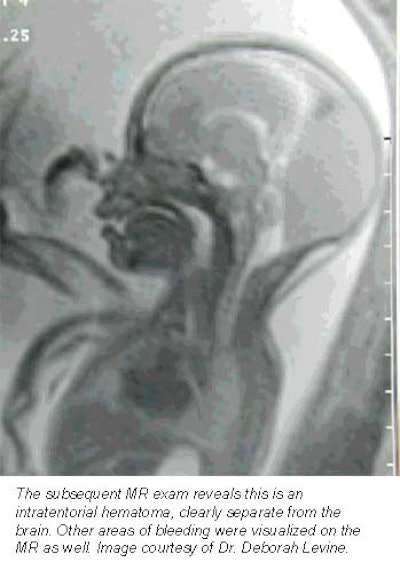

Still more applications are being pioneered at Boston’s Beth Israel Deaconess Medical Center, where researchers are nearing the end of a five-year study funded by the National Institutes of Health to evaluate how MRI complements prenatal ultrasound in the diagnosis of central nervous system disorders. So far, their results are promising.

"MR almost always will make you more sure of your diagnosis," said associate professor of radiology Dr. Deborah Levine. "It informs how we counsel the patient. Sometimes it directs the mode and timing of delivery, or helps a patient decide whether to terminate a pregnancy."

Levine, who oversees about one prenatal MRI exam per week, said she finds the modality especially helpful in determining whether fetuses suffer from central nervous system anomalies, as well as for defining many chest masses. Some radiologists are also using MRI to get a better idea of fetal volume, particularly in abnormal fetuses that are either too large or too small, she said.

Basically, MR is helpful whenever ultrasound is unclear, Levine said -- a general rule of thumb that’s allowed the procedure to catch on at institutions nationwide.